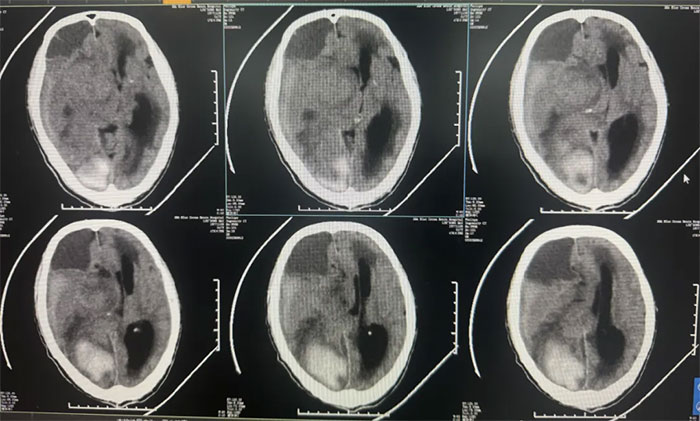

右顶枕叶出血,右侧额颞顶部亚急性硬膜下血肿,大脑镰下疝形成。

14天前突发神志不清,外院查头颅CT提示“脑出血,脑疝形成”。未手术,予脱水降颅压等保守治疗。